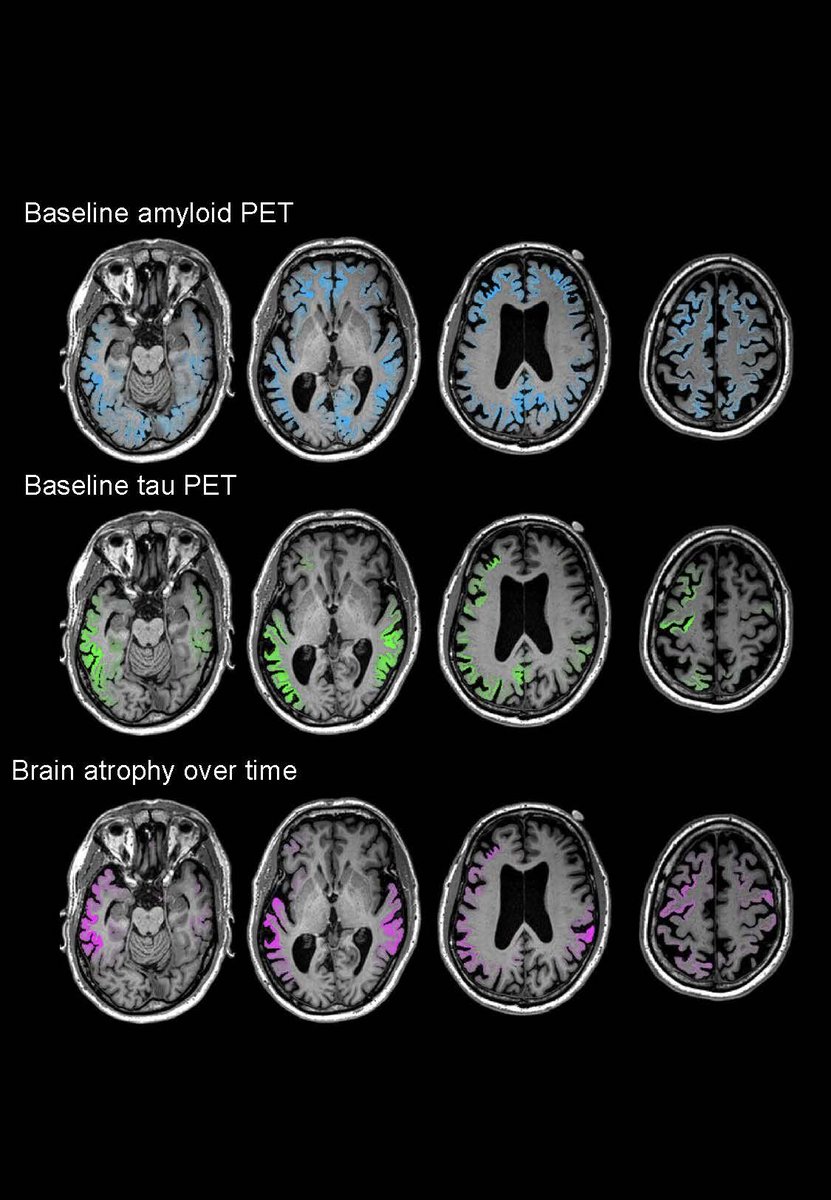

Tau "far surpasses amyloid in predicting toll on brain tissue" https://bit.ly/35mjlkD "Quantitative analyses showed that the global intensity of tau-PET, but not β-amyloid–PET, signal predicted the rate of subsequent atrophy" https://stm.sciencemag.org/content/12/524/eaau5732 …pic.twitter.com/UDibdrxNYS